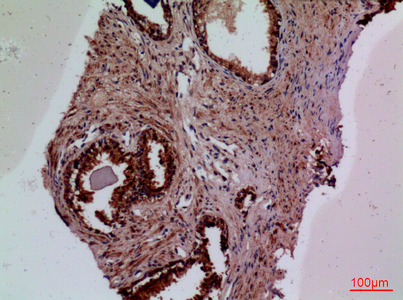

Anti-F3 Antibody

- Product NameAnti-F3 Antibody

- Scientific DescriptionRabbit polyclonal antibody to F3.